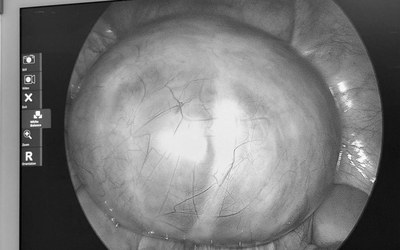

Người phụ nữ suýt mù mắt vì ký sinh trùng "ẩn náu", bác sĩ điểm mặt thói quen ăn uống "cực độc" nhiều người đang coi thường

Sức khỏe Thứ 4, 20/05/2026 | 04:00

Một ca bệnh kỳ lạ khiến các bác sĩ không khỏi bất ngờ khi ký sinh trùng bất ngờ xuất hiện trong hốc mắt của một người phụ nữ. Điều đáng nói là nguyên nhân phía sau lại bắt nguồn từ một thói quen mà ít ai ngờ tới.